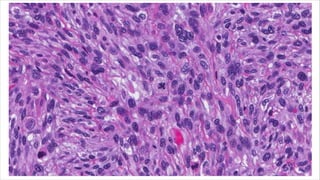

Epithelioid variant of leiomyosarcoma

• Rare neoplasm – Derived from myometrial smooth muscle.

• Diagnosis is based on > or = one of the following:

• Moderate to severe cytologic atypia.

• Tumour cell necrosis.

• >4 mitoses /10 high power fields.

• Growth pattern

• Arranged in nests, cords or sheets.

• Composed of round to polygonal cells with eosinophilic or clear

cytoplasm.